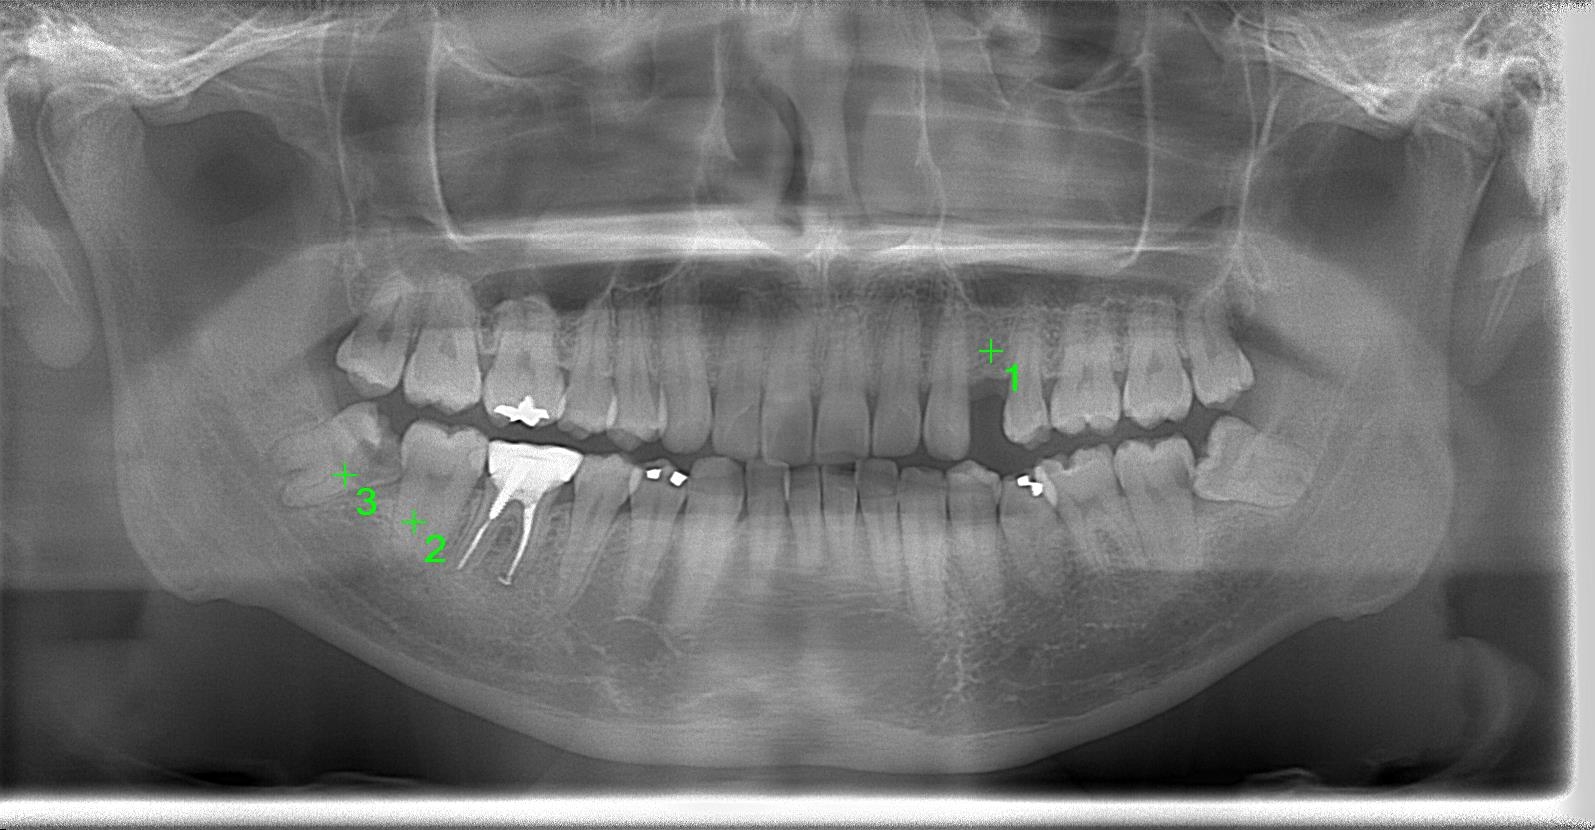

術前パノラマレントゲン写真